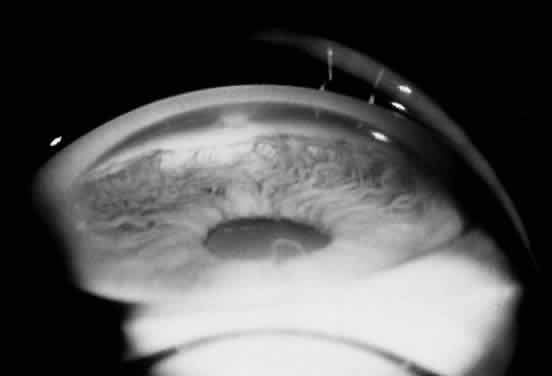

SCLEROCORNEA

In sclerocornea, the limbus is clinically indistinct, and opaque tissue extends into the cornea (Fig. 8). The curvature of the cornea is often flatter, similar to the sclera.4,94 Fine blood vessels arising from the conjunctiva may extend superficially over the peripheral cloudy cornea and terminate in arcades, leaving an avascular central area that may be opaque to clear.95 This condition is usually bilateral. In approximately 50% of the cases reported, a dominant or recessive inheritance has been described.95 Sclerocornea has been reported in association with numerous systemic abnormalities, including limb deformities, craniofacial defects, and genitourinary disorders.95,96 Histologic studies have demonstrated collagen fibers that resemble scleral collagen in their distribution and size. Bowman's membrane is usually absent, and Descemet's membrane and the endothelial layer are attenuated or absent.97,98

Fig. 8. Sclerocornea. (Courtesy of James J. Reidy, MD)